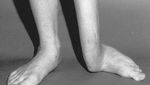

Jakarta - Sebuah studi medis membagikan penampakan kondisi langka yang membuat kaki bocah panjang sebelah. Pasien menjalani operasi khusus untuk memperbaikinya.

Semua pasien menunjukkan hasil baik. Kaki menjadi lebih simetris, fungsi berjalan membaik, dan deformitas terkoreksi. (Foto: The Journal of Bone & Joint Surgery)